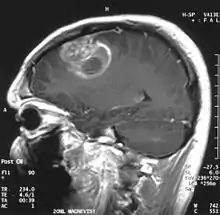

| Coronal MRI with contrast of a glioblastoma in a 15-year-old male | |

.jpg.webp)

When viewed with MRI, glioblastomas often appear as ring-enhancing lesions. The appearance is not specific, however, as other lesions such as abscess, metastasis, tumefactive multiple sclerosis, and other entities may have a similar appearance.[42] Definitive diagnosis of a suspected GBM on CT or MRI requires a stereotactic biopsy or a craniotomy with tumor resection and pathologic confirmation. Because the tumor grade is based upon the most malignant portion of the tumor, biopsy or subtotal tumor resection can result in undergrading of the lesion. Imaging of tumor blood flow using perfusion MRI and measuring tumor metabolite concentration with MR spectroscopy may add diagnostic value to standard MRI in select cases by showing increased relative cerebral blood volume and increased choline peak, respectively, but pathology remains the gold standard for diagnosis and molecular characterization.